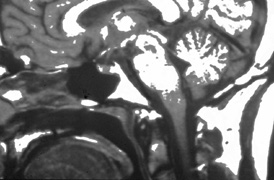

Anterior visual pathway gliomas account for the majority of intrinsic optic nerve tumors in childhood (Figs. 11, 12). Although they are true neoplasms, malignant features are extraordinarily rare in the pediatric population (see Chapter 5). Dutton58 provided a thorough review of this subject. When the glioma is initially confined to the optic nerve alone, the mortality rate is 5%. However, when the hypothalamus is involved, survival is less than 50% in some series. With a typically indolent course, these tumors generally can be managed conservatively, especially when confined to the optic nerve. Hoffman et al59 reviewed 62 cases of optic pathway/hypothalamic gliomas over a 14-year period, with 48 of these exhibiting relative stability with only visual defects: six patients had significant neurologic abnormalities, and eight died. Gayre et al60 reported a series of 42 patients with optic gliomas seen over 28 years at a single institution. Two-thirds were female, and slightly over half had neurofibromatosis type I (NF-1). Presenting signs and chiasmal involvement were similar in both NF (+) and NF (–) groups, the latter usually occurring within the first year after diagnosis. Regardless of treatment, the eye with better vision tended to remain stable over the long-term (and vision in the poorer eye often declined). Spontaneous regression of optic gliomas with visual improvement also has been reported.61,62

Fig. 11. Magnetic resonance imaging scans of optic gliomata. A. Marked enlargement of optic chiasm on coronal image. B. T1-weighted, gadolinium-enhanced image showing enlargement and marked enhancement of the right optic nerve and chiasm.